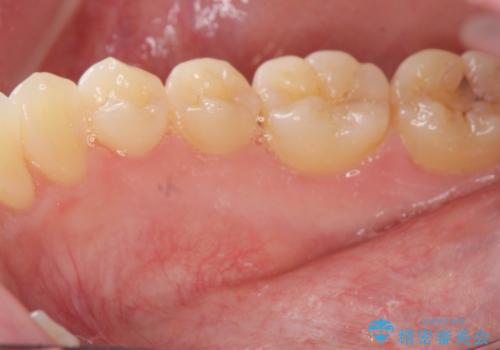

矯正の後戻りを防ぐ骨隆起の切除

このあと、両側の隆起を除去し、舌の収まりが楽になったと喜んでいただくことができました。